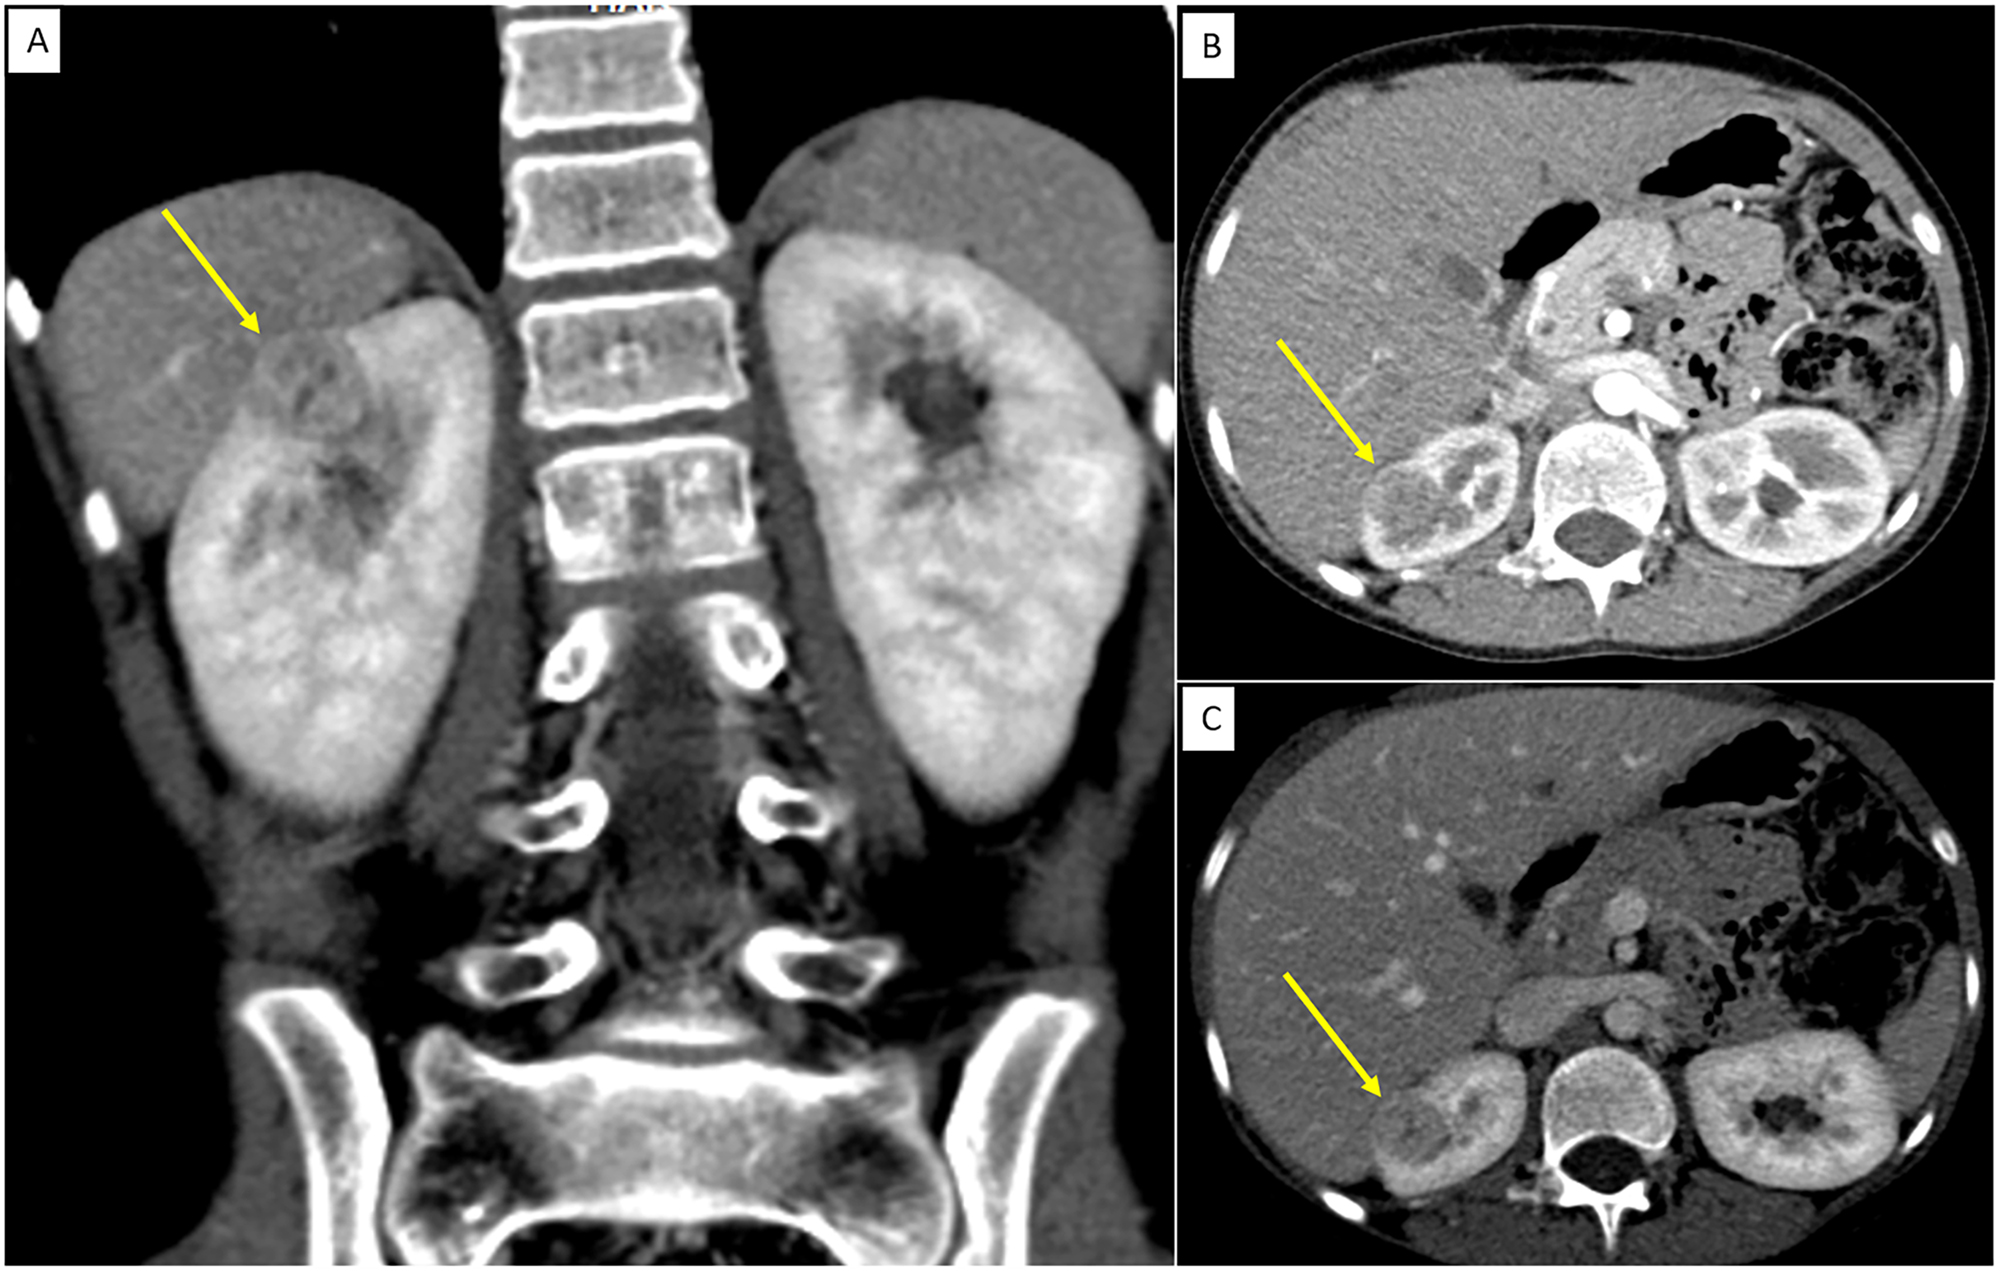

Reninoma: an unusual cause of growth failure

Nupoor Vaghasia, Ganesh Jevalikar, Mohammad Shafi Kuchay, Lipika Lipi, Ambrish Mithal

Page range: 73-78